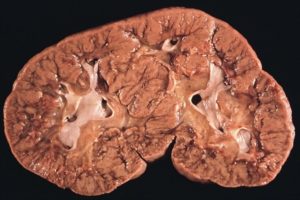

Опухолью Вильмса (аденосаркомой или нефробластомой) называют солидную высокозлокачественную почечную опухоль.

Мутированная примитивная ткань разного вида становится для нее основой еще при внутриутробном развитии плода.

Чаще онкогенными становятся клетки-предшественники ткани почек и незрелые клетки-предшественники ткани мышц, хрящей и эпителия. Поэтому нефробластома – это смешанная опухоль.

Опасен ее стремительный рост и ранние метастазы, поэтому в 10% случаев диагностику проводят, когда признаки рака почек у детей становятся явными и определяются метастазы. Вначале их находят в соседних с почками лимфатических узлах, затем – в легких и печени. Некоторые дети страдают от нефробластомы сразу двух почек. Она растет из незрелой эмбриональной нефроблатоматозной ткани почек.